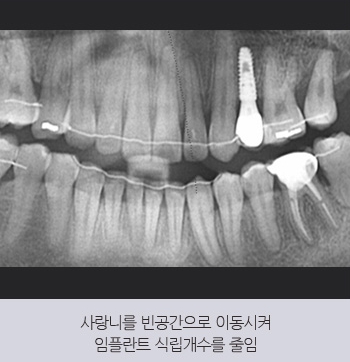

목동치과에서는 교정 치료와 협진을 통해

식립 개수를 줄이는 전략을 세웁니다.

30대 남성 환자분이 다른 치과에서

5개 임플란트를 권유받고 내원하셨습니다.

본원에서는 돌출입을 개선하는

교정 치료를 함께 진행하여

기존 치아를 활용할 수 있도록 유도하였고,

사랑니를 이동시켜

빈 공간을 채우는 방법을 적용하였습니다.

그 결과, 식립 개수를

5개에서 1개로 줄일 수 있었습니다.

또한, 교정 치료를 통해 잇몸뼈의 높이가 올라가

건강한 상태로 회복되었으며,

입술 라인이 개선되어 심미적인 효과까지

함께 얻을 수 있었습니다.